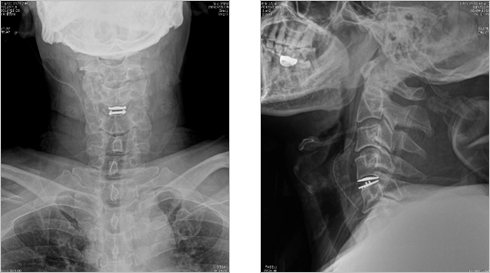

척추관절 이미지 자료

경피적 전방 고정술

경피적 후방 고정술